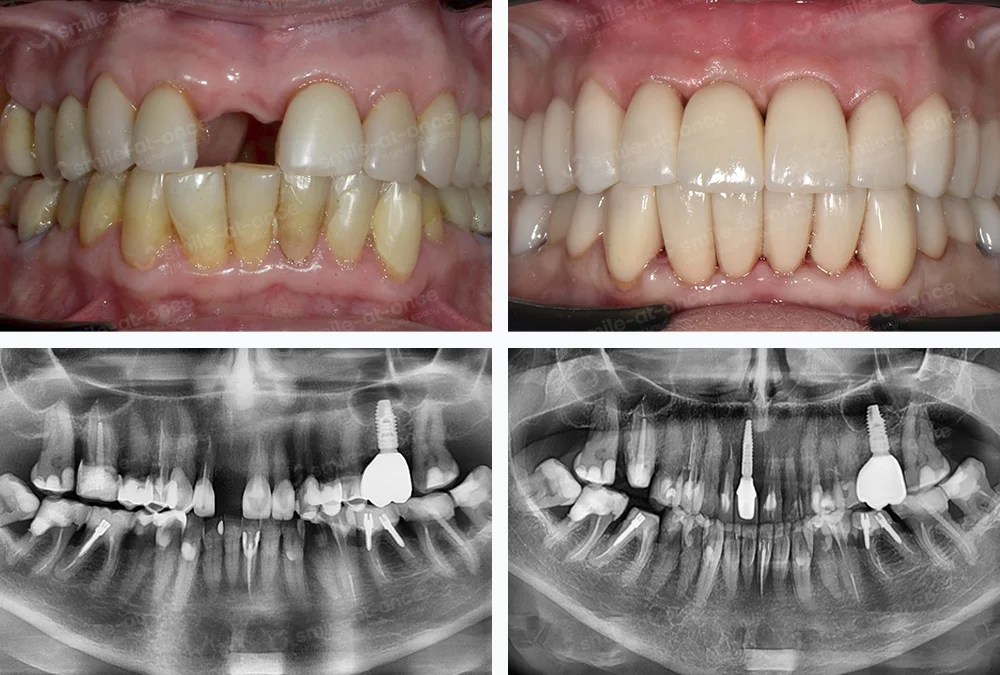

Аксиография — ранний сдвиг диска, КТ — уплощение суставной поверхности, 3D-скан — «короткие» пломбы, потеря шестого зуба.

План: жёсткая индивидуальная шина ночью, мягкая коррекция контактов, физиотерапия → возврат высоты на временных коронках → имплант на место моляра.

Через 6 месяцев щелчок ушёл, открывание стало симметричней, голова «отпустила».

Показан при тяжёлой стираемости, множественных утратах зубов, деформациях прикуса.

- Комплексное протезирование с восстановлением окклюзионной высоты на всех зубах.

- Имплантация и несъёмные конструкции по показаниям; при необходимости подключаю хирурга-имплантолога Евгения Жиленко.

- Современные протоколы полной реабилитации (All-on-4/All-on-6, гибкие схемы с немедленной нагрузкой), цифровое планирование, хирургические шаблоны.

Перед протезированием я делаю цифровое моделирование: совмещаю 3D-сканы зубов, фото лица и траекторию движения мыщелка. Это как репетиция спектакля: мы видим высоту нижней трети, линии улыбки, будущие контакты. Так меньше сюрпризов и для эстетики, и для ВНЧС. Совет: просите показать «до/после» в цифре — решение принимать легче.

Этапы протезирования при полной реабилитации